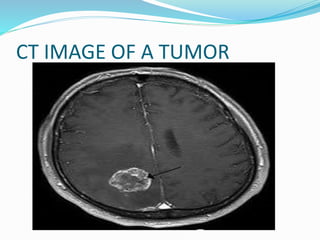

CT IMAGE OF A TUMOR

 CT: used as a screening study to determine

whether a lesion is present (often at presentation

to an emergency department); also used to

evaluate bone, blood, and calcification